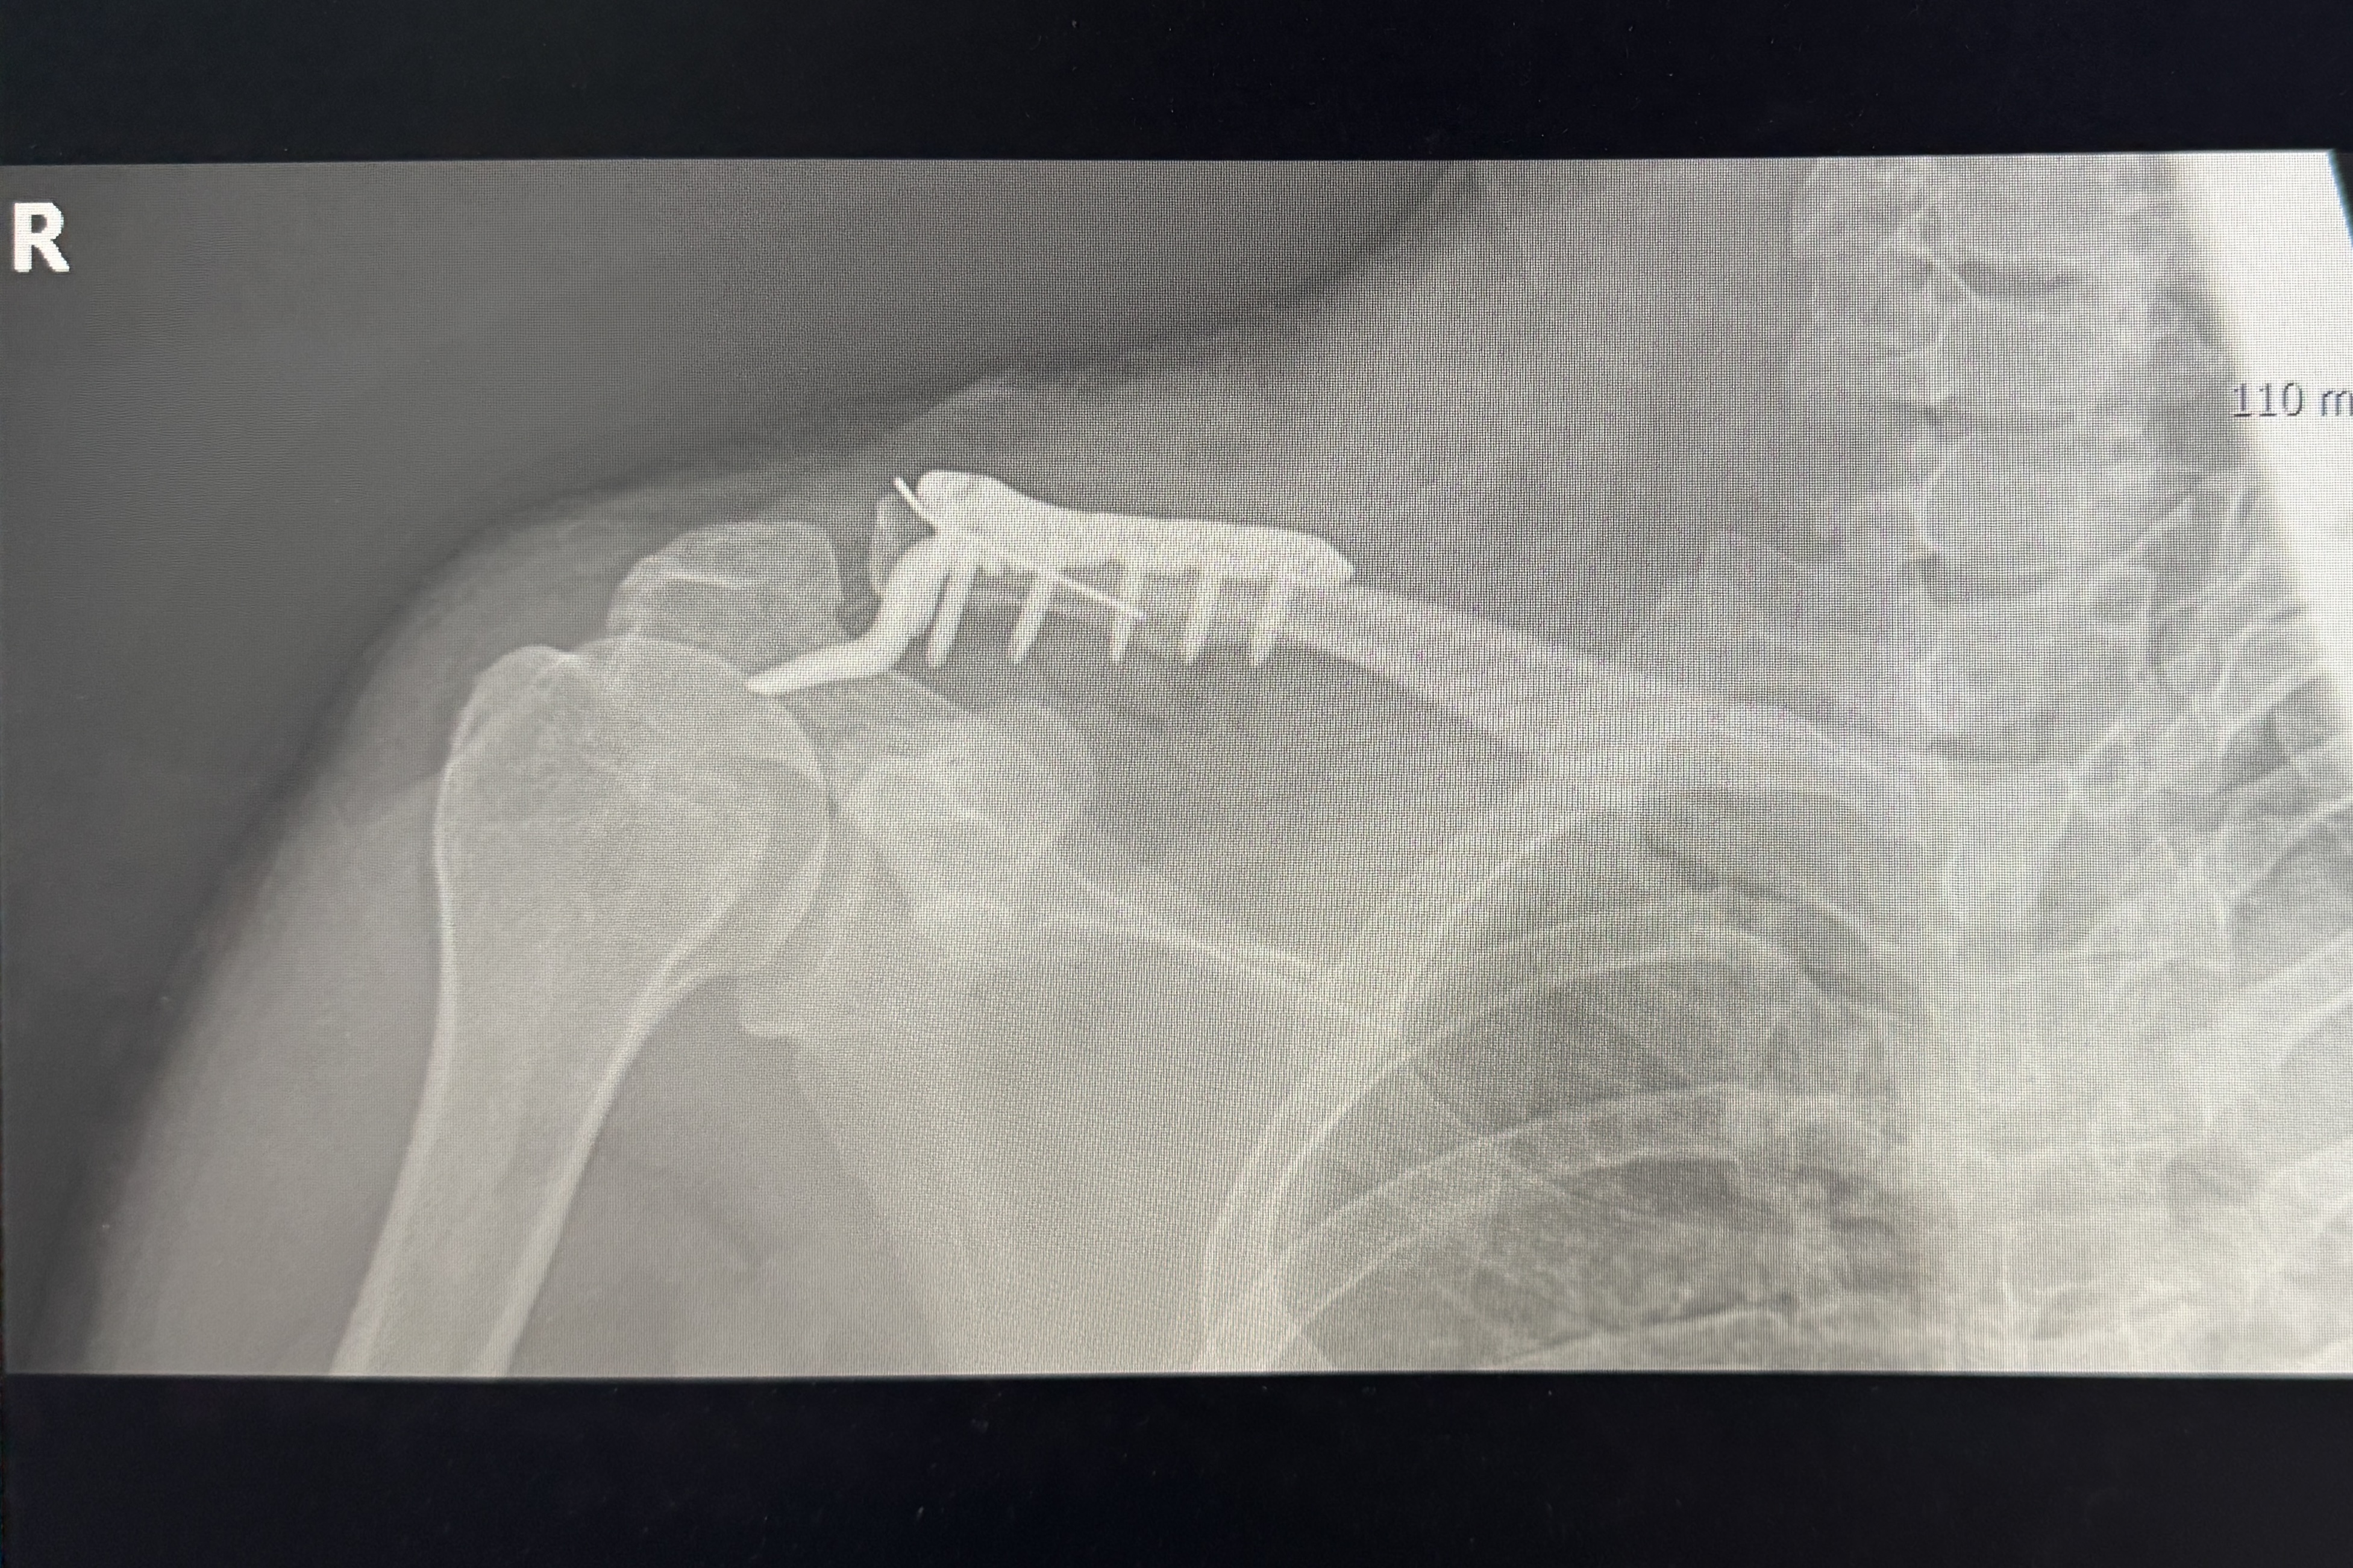

몇 분이나 지났을까, 어깨가 마구 부풀어 오르기 시작했다. 급하게 회사 인근에 있는 정형외과 응급실을 찾았다. 처음에는 탈골정도로 생각했는데 의사가 엑스레이를 보더니, "어깨가 아니라 쇄골이 부러졌네요. 수술하셔야 해요"라며 마치 이 맘 때쯤은 흔하게 있는 일이라는 듯이 무심하게 말했다. 상급 병원으로 가서 수술해야 하지 않겠냐는 물음에 의사는, 지금 대형 병원은 의료 파업 때문에 당장 수술을 못하고 한참을 대기해야 하고, 지금 다친 부위는 이대로 뼈가 붙어버리면 일이 커진다고 했다. 하여 더 고민 없이 입원을 결정하고 바로 다음 날 아침 수술을 했다.

이렇게 어이없게 다치고, 수술까지 하게 될 줄이야. 저렇게 철심을 박고 3개월 뒤에는 철심을 제거하는 수술까지 받아야 한다고 했다. 완전히 예전처럼 돌아가는데 1년 정도를 봐야 하고, 다쳤을 때 인대가 손상되어서 최악의 경우에는 끊어진 인대도 수술을 받아야 한다는 소식까지.